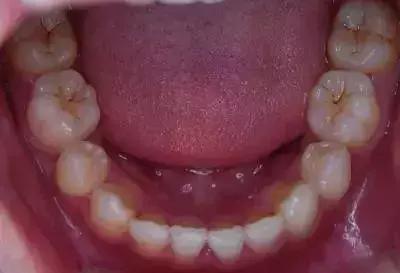

牙齿咬合面出现黑线一般有两个原因:单纯的色素沉着和蛀牙。

如果你的牙齿是第一种情况,那就不用担心,往往是刷牙不彻底造成的,通过洗牙就可以轻松去除。但是如果置之不理的话,他们有可能会沉积于龈下缝隙,出现在牙齿根部和颈部,影响健康和美观。

有条件的话,建议可以去做一个窝沟封闭来预防蛀牙(成年人也可以做的);定期洗牙